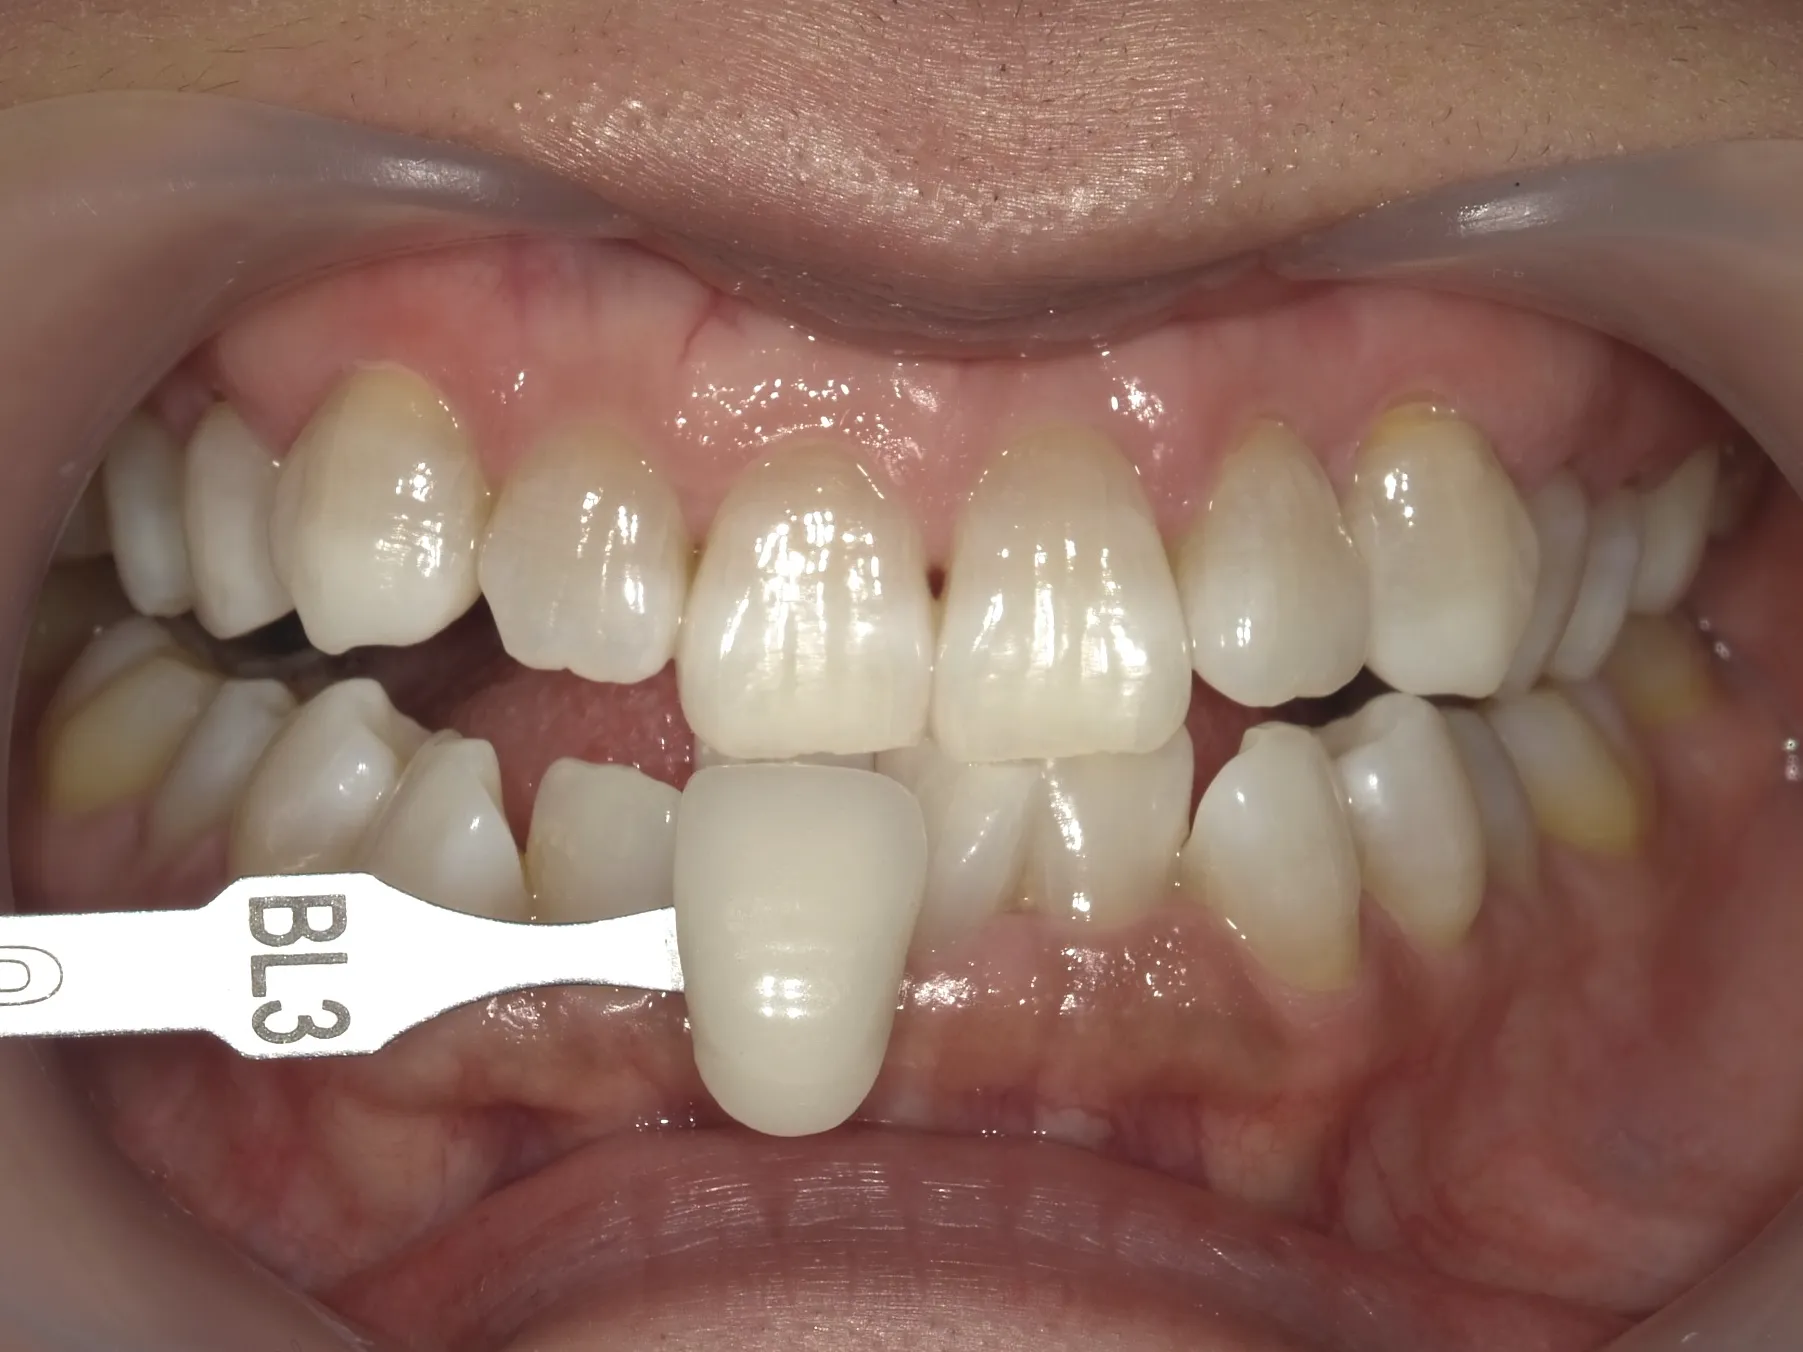

ホワイトニングは歯を削らないため、削らずに白くしてみたいという方に最適な治療法です。

特に、オフィスホワイトニングとホームホワイトニングを併用する

「デュアルホワイトニング」が効果的です。

| ホワイトニング | 非侵襲的で歯を削る必要がない 全体的に白くできる |

テトラサイクリン歯による深い着色には限界がある |